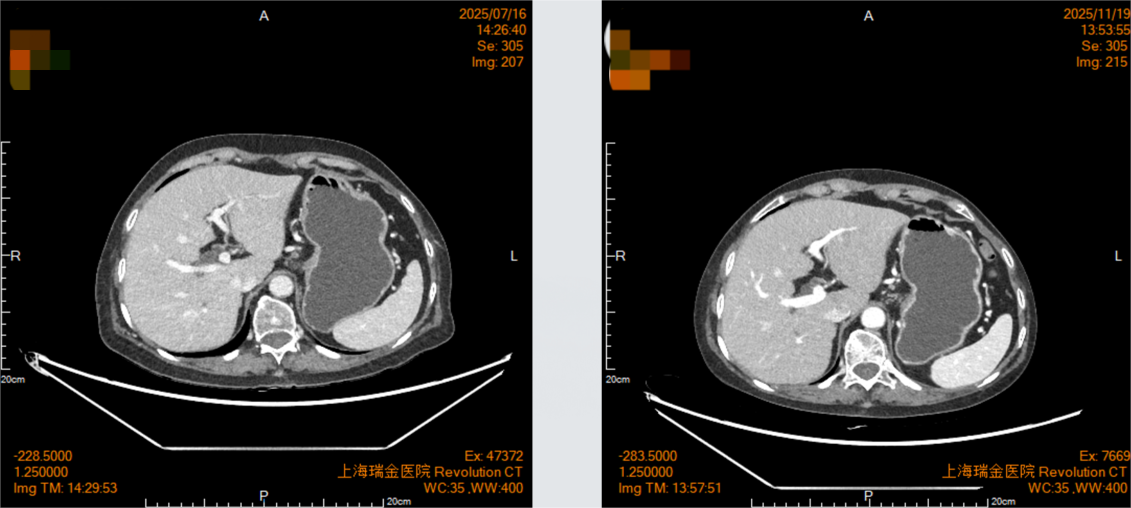

2025年7月16日复查影像学显示,贲门癌化疗后,贲门胃壁稍增厚;双肺间质性改变。

2025年11月19日复查影像学显示,贲门癌化疗后,贲门胃壁稍增厚;贲门部肿物及转移淋巴结较前明显退缩,影像表现为接近CR(无可评价病灶)。

MDT讨论:影像科:患者目前肿瘤退缩明显,影像表现接近CR(无可评价病灶),可进一步完善PET检查。肿瘤科:患者目前疗效评估部分缓解(PR),有CR可能,可继续维持原方案化疗,可完善胃镜检查多点取病理,以评估是否达CR。普外科:患者免疫治疗效果理想,目前肿瘤退缩明显,有手术指征,可考虑行手术治疗。消化科:患者单次PD1治疗即出现重度免疫性肝炎,虽经短暂激素治疗后即好转,但不排除PD-L1治疗后再次出现免疫性肝炎,需密切监测其肝功能变化。